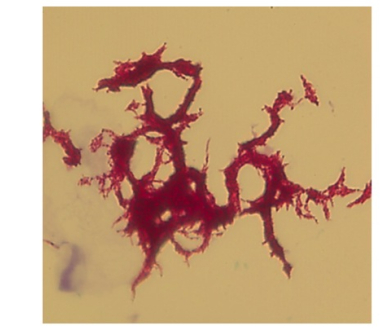

April 14 | The isolate was also referred to the Wadsworth Center Mycobacteriology Laboratory by the NYC PHL for whole genome sequencing. DNA sequencing is performed to detect mutations in certain genes, indicating drug resistance. |

April 25 | The Wadsworth Center Mycobacteriology Laboratory reported results indicating the presence of mutations in the following genes: rpoB (rifampin), katG (isoniazid), inhA (isoniazid), pncA (pyrazinamide), embB (ethambutol) and rpsL (streptomycin). The tests confirm the drug susceptibility findings of the NYC PHL. In addition, a mutation in gyrA was detected, predicting resistance to fluoroquinolone, a major class of second line drugs for treatment of MDR strains. This was crucial information that allowed the treating physician to modify the ongoing drug regimen prior to the availability of results from conventional second line drug susceptibility testing. |